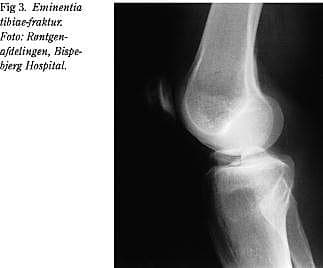

Hyppige samtidige skader

Artroskopisk synlige bruskskader ses hos ca. 10%, men ved MR-scanning kan der hos over 50% påvises et kraftigt knogleødem (bone bruise) i den laterale femurkondyl i månederne efter en korsbåndsskade (Fig. 2), og biopsier tyder på, at forandringerne når helt ned i brusken. Det vides ikke, om bone bruise disponerer for slidgigt, men det kan være årsagen til, at nogle patienter har meget ondt, når de støtter på knæet i månederne efter en korsbåndsskade.